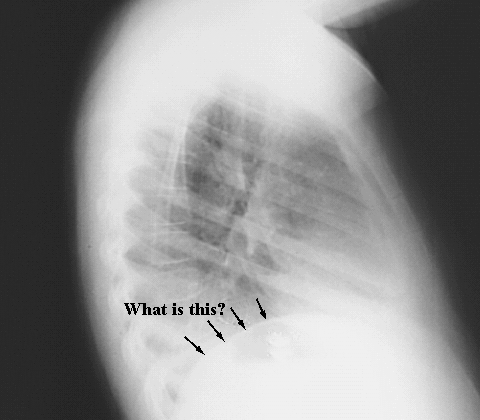

Thorax- Chest lateral Diaphragm

Arrows: Left dome of the Diaphragm.